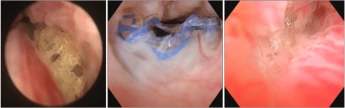

Mesh erosion in the urethra on cystourethroscopy.

Source: Han, Ji-Yeon. (2019). Recurrent Urinary Tract Infection from Urethral Mesh Erosion after

Midurethral Mesh Sling Surgery. Urogenital Tract Infection. 14. 60. 10.14777/uti.2019.14.2.60.